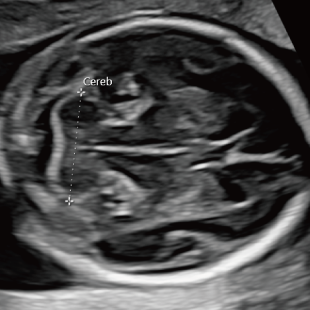

Voluson Expert 22®(GEHealthcare)という産婦人科領域におけるハイエンド超音波診断装置を使用しています。 従来機種と比べ、より高精細な画像描出性能と高度な解析機能を備えており、 胎児の発育や形態をより詳細に観察することが可能です。

通常の妊婦健診で行う超音波検査では、主に胎児発育(推定体重)、羊水の量、胎児の向きを確認しています。一方で健診の限られた時間内では、胎児を詳細かつ系統的に評価することが難しい場合があります。当院で行っている胎児超音波スクリーニングとは、高性能な超音波検査機器を用いて胎児の発育や形態(からだの構造)をより詳しく観察し、胎児の状態を丁寧に評価する検査です。 出産前に赤ちゃんの状態をより詳しく知りたいという患者さんのご希望にお応えするため、当院では超音波検査士*および超音波専門医・指導医**が胎児超音波スクリーニングを担当します。